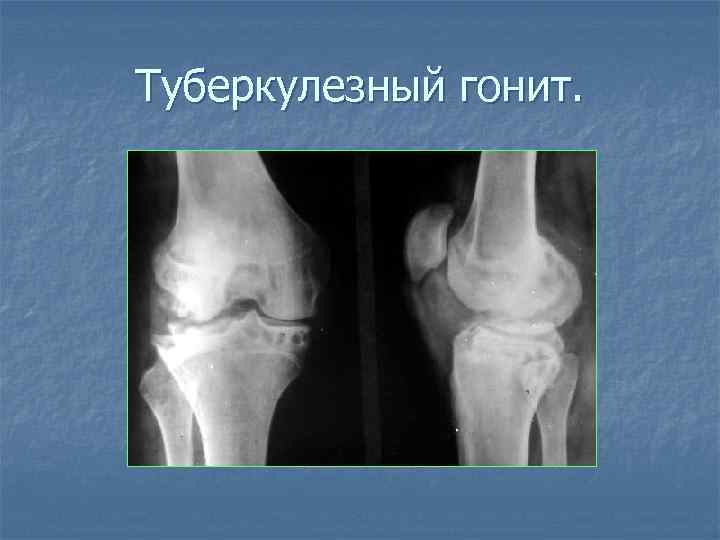

Туберкулезный гонит.